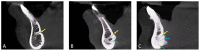

Background: This study aimed to evaluate the midline mandibular lingual canals and foramina and their anatomic variations using CBCT scans.

Methods: This study used retrospective analysis. A total of 320 CBCT scans were used to evaluate the study parameters, which comprised the presence or absence of the mandibular lingual foramen (MLF)/mandibular lingual canal (MLC) and its category, the distance between the buccal cortex and the start of the MLC, the distance between the inferior border of the mandible and the superior border of the foramen at its lingual and buccal terminals. The length and diameter of each canal at its lingual and buccal terminals.

Results: MLC was found in all included CBCT scans. Out of 320 included CBCT scans, a single canal was represented by 30.9%, double canals (Supra with Infra -spinosum) configuration appeared in 54.7%, and triple canals (Supra-Inter-Infra) represented 14.7%. The supraspinosum canals averaged 5.81 ± 2.08 mm in length and 0.87 ± 0.30 mm in diameter at the lingual terminal. In terms of the number of canals, there was a significant difference between men and women (p ≤ 0.001), with 60% of the men in the sample having double canals and 43.1% of the women having single canals. Moreover, the male gender had a higher prevalence of triple canals (21.3% vs. 8.1%) than females. Males and females were distributed equally among the supraspinosum canals, with no statistically significant difference (p ≤ 0.7). A considerable increase in the finding of interspinosum and infraspinosum canals was seen in the male sample (p ≤ 0.001).

Conclusions: midline mandibular canals were found in all investigated CBCTs of the sample of both sexes; however, the anatomy and location of the MLF and canals varied significantly among the Saudi population.